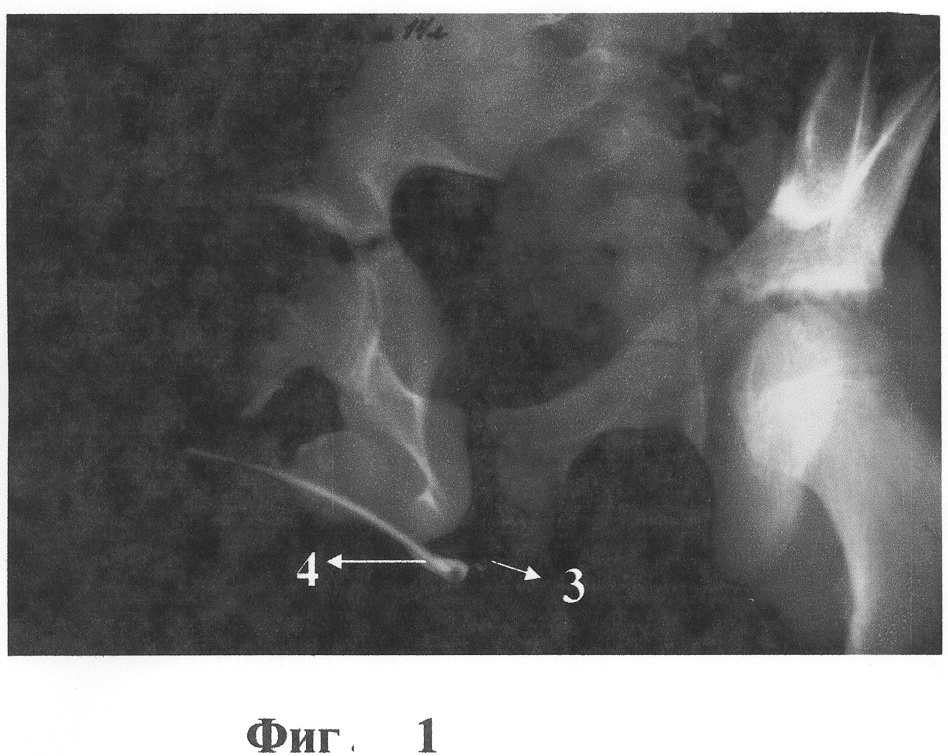

Ниже приводится подробное описание предлагаемой методики. Исходное патологическое состояние представлено на фиг.1, 2, где 1 – мочевой пузырь, 2 – проксимальный отдел здоровой уретры, 3 – участок стеноза, 4 – дистальный отдел здоровой уретры.

На снимках и уретроскопии отмечается стриктура уретры значительной протяженности от бульбарного до простатического отделов. Проходимость почти полностью отсутствует. Фиг.1, 2. В день поступления наложена пункционная эпицистостома.